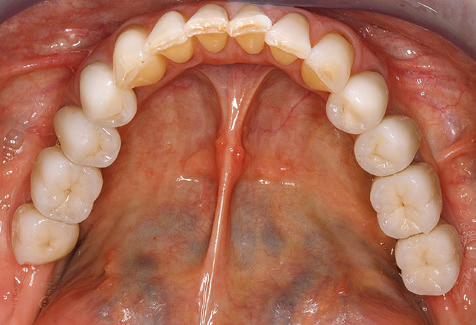

Due to the presence of periodontal disease, SPT was performed every three months in the first years following the insertion. The patient demonstrated a high degree of motivation and good compliance. The pocket depths recorded annually revealed a stable periodontal situation with a BOP index of below five per cent. On the basis of the stable periodontal situation and good cooperation on the patient’s part, the recall interval was extended to every six months as of the sixth year of the prosthetic function phase. Following the change in the recall interval, the respective annual documentation of the periodontal status continued to reveal a stable periodontal situation with no increase in the pocket depths and a BOP index below five per cent (Fig. 2a and b).

The ten-year check-up revealed no indications of advancing clinical attachment loss or peri-implant bone substance loss (Fig. 3).

Standardised and regular risk-adapted care in the scope of SPT is the key to treatment success for the clinical long-term success in periodontically compromised patients. This is particularly true for patients fitted with implants following successfully completed periodontal treatment (Fig. 11a and b).